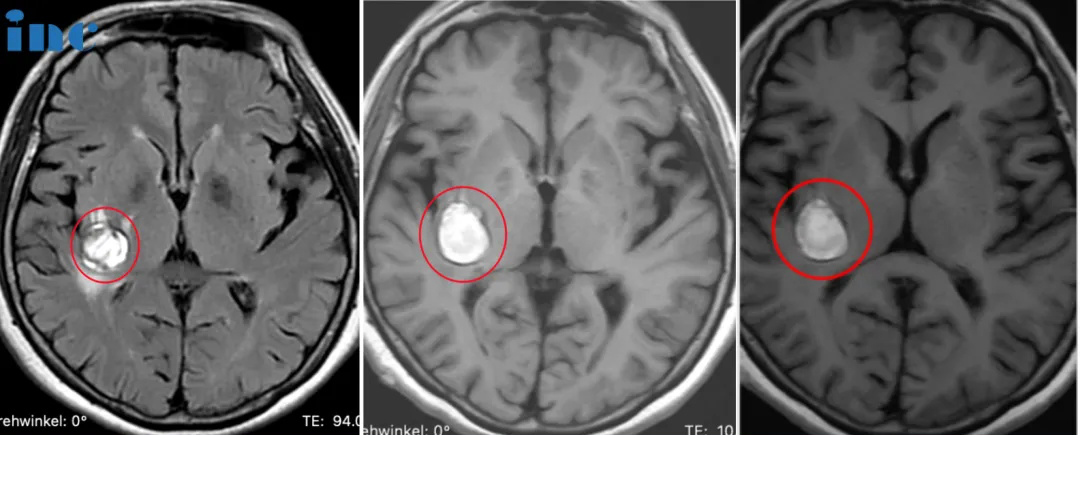

INC巴教授主刀手术后

术后核磁显示,海绵状血管瘤得到顺利全切,柯女士的状态也好,神采奕奕,和常人无异。术后2天巴教授查房时,已经可以下地走路。看到前来查房的巴教授,柯女士激动,亲切拥抱感谢巴教授,终于摆脱了危险的基底节海绵状血管瘤的她满怀感激得握住巴教授的手说道,“我要看看巴教授这双神奇的大手,这是上帝之手,巴教授感谢你!”

小磊术前MRI影像显示右额、颞、基底节区、侧脑室前角区占位

术前术后MR磁共振对比,术前右额、颞、基底节区、侧脑室前角区较大占位,压迫岛叶及脑室,脑室增大。术后MR提示肿瘤近全切,占位效应解除,无新发脑损伤等。